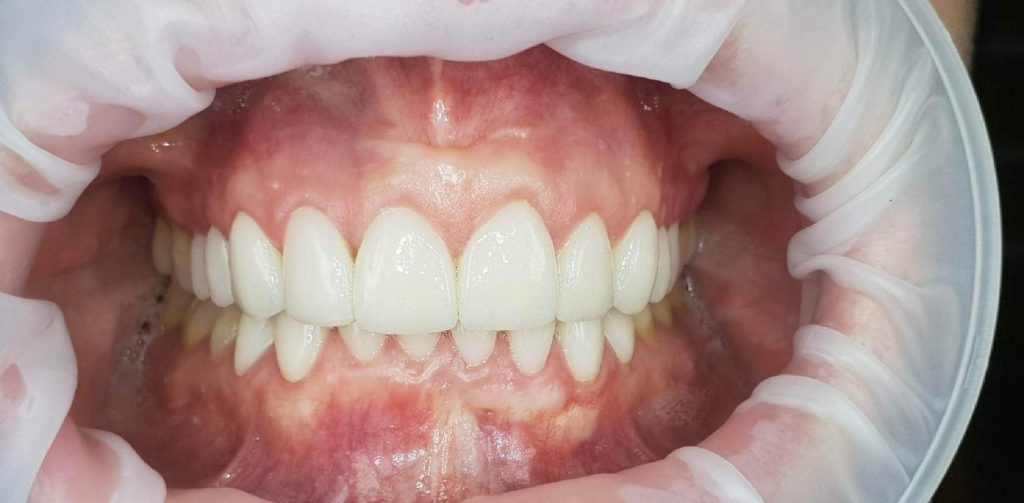

Następnie została wykonana wizualizacja nowego uśmiechu, idealnie dopasowana do twarzy Pacjentki. Po jej akceptacji, przygotowaliśmy komplet koron i licówek pełnoceramicznych na górne i dolne zęby.

Całe leczenie trwało zaledwie 3 miesiące!

Dzięki współpracy lek. stom. Michała Badowskiego i techn. dent. Joanny Gancarz z laboratorium Dentalscan Pacjentka zachwyca pięknym uśmiechem!